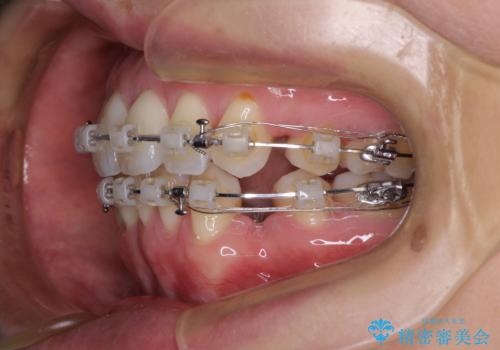

- クリアブラケット

- 2年3ヶ月

当初目論見通り、左右奥歯の咬み合わせはしっかりとさせることができました。

下唇に跡がつくほど飛び出していた上顎前歯も引っ込み、満足のいく仕上がりとなりました。